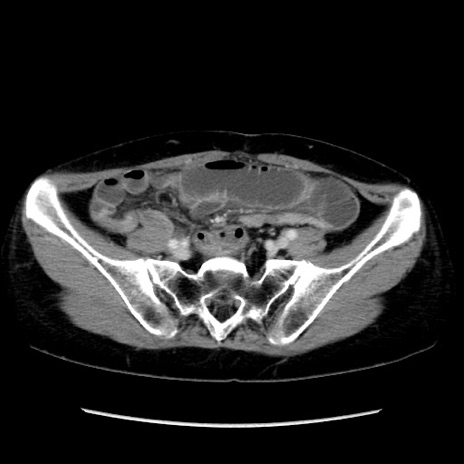

症例32(横断像)

【症例】40歳代 女性

【主訴】上腹部痛、嘔気・嘔吐

【現病歴】約9時間前頃から急に上腹部痛、嘔気、嘔吐が出現。改善しないため救急要請。

【既往歴】子宮頚癌(広汎子宮全摘術、放射線療法)、腸閉塞

【身体所見】腹部:平坦、軟、腸雑音亢進、上腹部を中心に腹部全体に圧痛あり。

【データ】WBC 8400、CRP 0.03